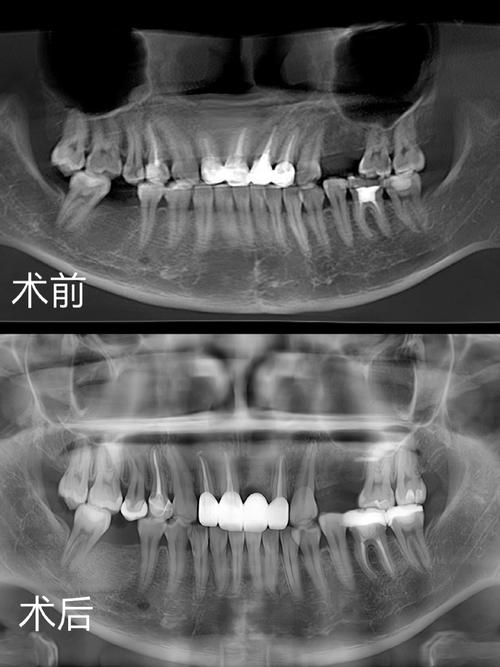

- 监测重点:每3个月拍摄根尖片,观察牙根长度变化、根尖孔形态及有无吸收迹象;临床检查牙齿松动度、叩痛,评估根尖周反应。

- 影像学检查:治疗初期拍摄根尖片、曲面断层片,评估牙根长度、形态;治疗中每6个月复查CBCT,三维观察根尖周骨密度、根尖孔形态及有无吸收;